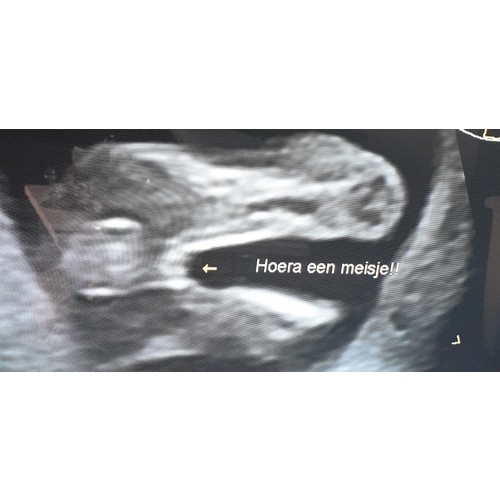

Wij hadden de geslachtsbepaling bij 15 weken precies. Die dame gaf aan dat ze het bij twijfel eerlijk zou zeggen. Ze liet het geslacht aan ons zien vanuit twee hoeken. Een meisje! Ook bij de 20 weken echo was het nog steeds een meid. Ik denk dat je vandaag de dag wel kunt vertrouwen op de kennis van die mensen. Zij doen de geslachtsbepaling ten slotte vaker dan een verloskundige zelf dat doet. (In ieder geval in mijn regio).

We hebben dinsdag de echo gehad. Ze heeft wel een kwartier gekeken en het is een meisje 💗. Ze zei ook 99% zeker dus echt heel bijzonder om het te weten. Haha toch stiekem een kleine angst dat het toch veranderd, niet omdat ik geen jongen wil, maar ik ga nu wel al lekker shoppen 🤭😊. We zijn nu 14w5d.